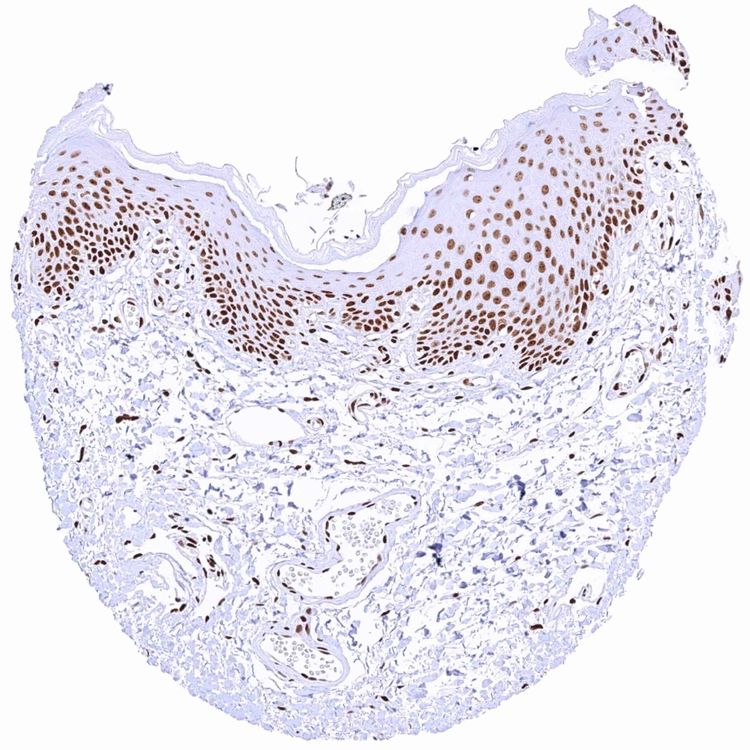

Anal canal, skin

Anal canal, skin – HMGB1 staining intensity is strongest in the basal and suprabasal cell layers and it countinuously decreases towards the superficial cell layers